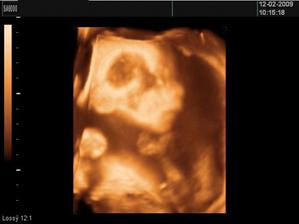

• 4.2.2009 - máme za sebou prvý 3D UTZ a už vieme že drobček bude EMILKO!!!